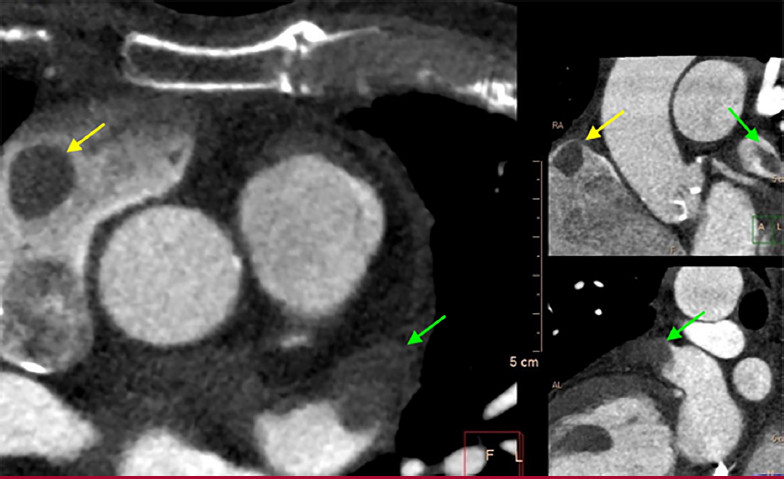

En el estudio se observan defectos de relleno de contraste en fases precoces y tardías en el techo de la aurícula derecha próximo a la orejuela y en orejuela auricular izquierda, compatibles con trombos (Figuras 1 y 2).

La tomografía cardiovascular es un excelente instrumento para evaluar trombosis auricular, que se observa como una estructura definida con bordes netos, que genera defectos de relleno del contraste tanto en fases precoces como tardías luego de la infusión del mismo (para distinguirlo de los fenómenos de rémora, que pueden tener defectos precoces que corrigen en fases tardías). Tiene una elevada sensibilidad y especificidad para detección de trombos en aurícula izquierda. 3 Sin embargo, no siempre es sencillo lograr un adecuado contraste de las cavidades derechas y particularmente la orejuela derecha, en especial en estudios dirigidos a evaluar “estructuras izquierdas” (coronarias, venas pulmonares, válvulas), por lo que una trombosis auricular derecha puede pasar desapercibida. La baja señal en unidades Hounsfield en la tomografía no contrastada o el ratio de las unidades Hounsfield entre trombo y la aorta utilizando equipos de doble fuente 4 pueden ayudar a la identificación de la trombosis auricular mediante tomografía cardiovascular.